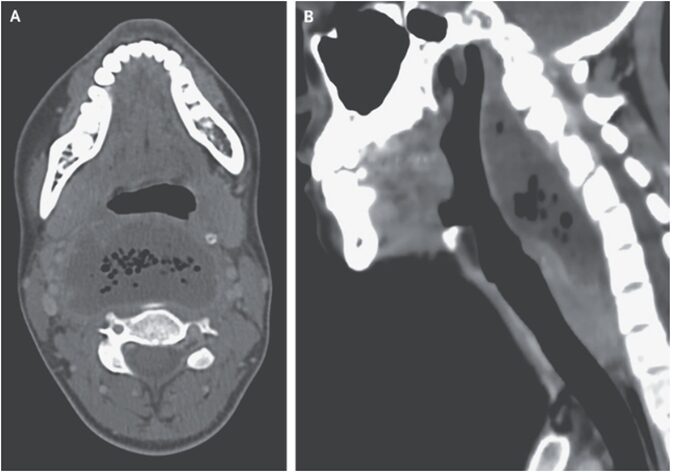

頚部CTでは咽頭後方に6.2×3.4㎝の液体貯留を認め、気泡と造影縁を認めた。

「咽後膿瘍」と診断。